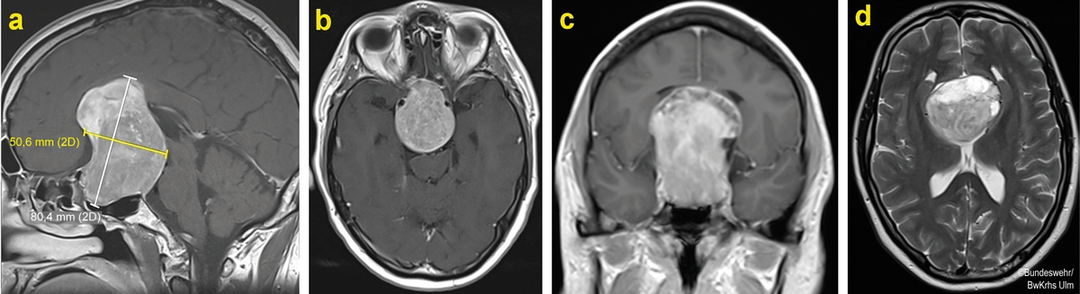

Wie die Versorgung eines Patienten mit Giant-Tumor ablaufen kann, verdeutlichen die Autoren u.a. am Beispiel eines 37-jährigen Patienten. Als dieser die Notaufnahme des Bundeswehrzentralkrankenhauses aufsuchte, litt er schon seit Wochen an einer progredienten Sehstörung. Er fühlte sich schlapp und wurde zunehmend durch Müdigkeit und Brechreiz geplagt. Die ophthalmologische Untersuchung ergab die für Hypophysenadenome typische bitemporale Hemianopsie und einen beidseits erheblich eingeschränkten Visus. Labordiagnostisch fielen eine Elektrolytstörung und ein stark erniedrigter Cortisolspiegel auf. Die übrigen Hormonspiegel waren unauffällig. In der MRT zeigte sich ein großer Tumor, der von der Sella ausging und bis zum Dach des Seitenventrikels reichte. Die wahrscheinlichste Diagnose: hormon­inaktives Giant-Adenom.

Über einen transnasalen Zugang gelang es zwar, einen Großteil der Tumormasse in der Sellaebene zu entfernen. Die vollständige Resektion scheiterte jedoch an der Festigkeit und Unbeweglichkeit des Adenomgewebes sowie der starken Blutungsneigung. Ein weiteres Problem: Anteile des Tumors reichten weit suprasellär bis ins Ventrikelsystem und verlagerten sich auch nicht spontan zur Sella hin. Daher erfolgte im zweiten Schritt die transkranielle Resektion über einen transfrontalen-transkortikalen Zugang zum rechten Seitenventrikel. Doch auch jetzt war keine komplette Entfernung des Tumors möglich. Immerhin senkte sich das verbliebene adenomatöse Gewebe innerhalb weniger Wochen spontan in die Sellaebene, wo es wiederum per transnasalem Zugang in der Masse dezimiert werden konnte. Der nicht entfernbare kleine supraselläre Rest zeigte bis zwei Jahre nach dem letzten Eingriff weder eine Wachstumstendenz noch verursachte er klinische Symptome. Die Sehfähigkeit des jungen Patienten hatte sich deutlich verbessert. Er benötigte zwar noch eine Kortisolsubstitution, wies aber keine weiteren hypophysären Funktionsstörungen auf. Eine Komplettresektion des verbliebenen Tumorgewebes könnte über einen transkraniellen-pterionalen Zugang zwar gelingen, ist aber nur dann indiziert, wenn sich eine Wachstumstendenz zeigt oder endokrine Symptome auftreten. Als Alternative böte sich eine stereotaktische Einzeitbestrahlung an. Aufgrund des stabilen Befundes und in Übereinstimmung mit der Leitlinie entscheiden sich Dr. Schulz und seine Kollegen bei ihrem Patienten für ein abwartend-kontrollierendes Vorgehen.